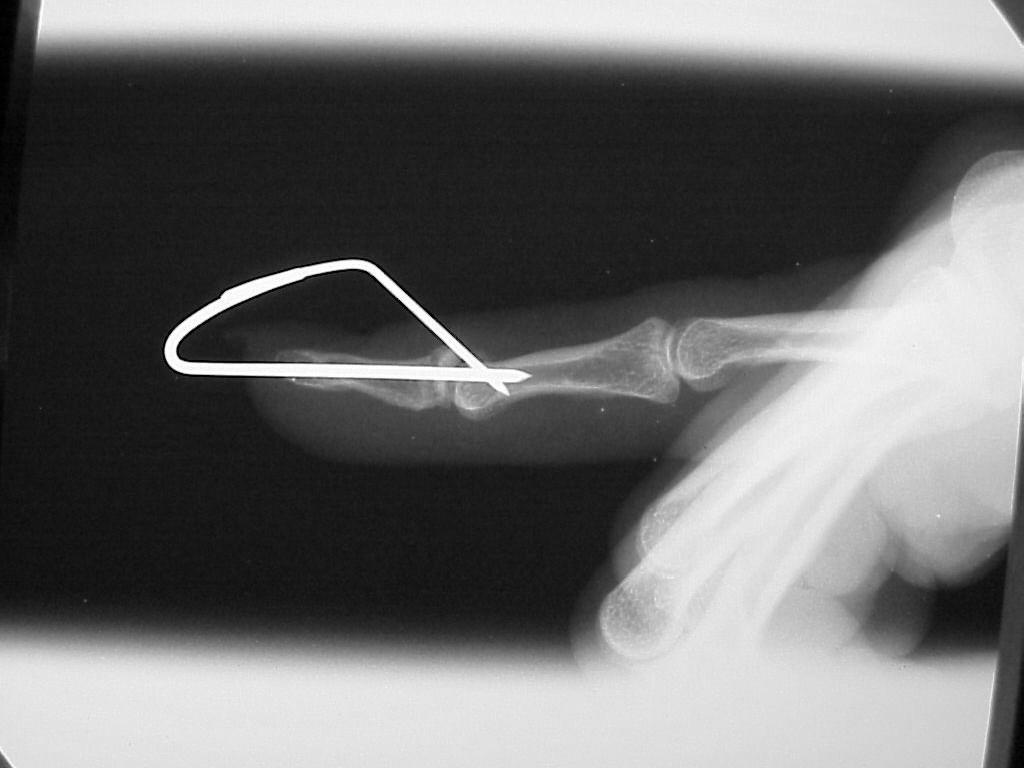

Case 3

Acute mallet fracture treated with percutaneous

pinning: proximal pin stabilizes the fracture

fragment, longitudinal pin maintains distal phalanx

position. |

| Thermoplastic bonding of the protruding ends: appearance at one month. |